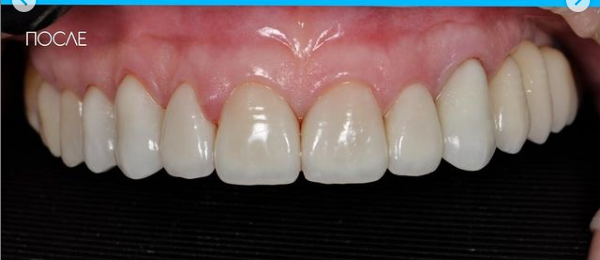

Установка коронки на зуб

Провели швейцарскую профгигиену. Перелечили зубы с несостоятельными пломбами и воспалениями. Удалили 7 зубов на верхней и нижней челюсти с одномоментной имплантацией 9 имплантатами, костной пластикой и пластикой десны. После приживления имплантатов установили временные коронки. Изготовили и установили абатменты Procera и 28 единиц керамических коронок EMAX.